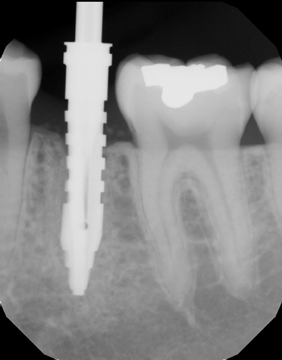

I started with the capture of a post-extraction i-CAT CBCT scan (Fig. 4), focusing in on the area of interest. I reviewed the implant site carefully and also used the Hounsfield tool in Tx STUDIO to assess the density of the area, which was 662 HU (Fig. 5).

Fig. 5 Fig. 6